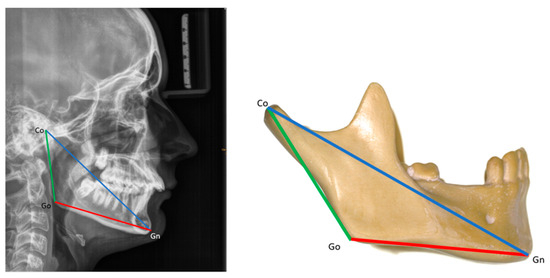

Background: The aims of the study were to describe facial morphology and analyze facial growth in adolescents with Robin sequence (RS) or Stickler syndrome. Methods: The facial morphology, mandibular size, and facial growth of 69 adolescents (ages 12–18) with RS were analyzed using existing cephalometric radiographs (n = 37) and photographs (n = 69). All participants were followed in our institution since birth. None underwent growth-modifying treatment for micrognathia during infancy, but all had conservative orthodontic treatment during adolescence. Results: Cross-sectional cephalometric analysis according to Tweed revealed differences in RS adolescents as compared with reference values, such as a proportionate retrusion of both jaws, as indicated by decreased SNA and SNB angles (p < 0.05). This finding was mostly associated with skeletal Class I (62.2%) and a vertical facial pattern as indicated by increased FMA and CoGoMe angles (p < 0.05). In Delaire’s analysis, patients showed decreased maxillary, maxillary alveolar (p < 0.05), and mandibular body territories (p > 0.05) but increased ramus (p > 0.05) and nasopremaxillary territories (p < 0.05). According to Ricketts’ analysis, mandibular width was decreased in half of our patients (p > 0.05). The mandibles were harmoniously downsized before and after the growth spurt (p < 0.05); however, they exhibited greater growth velocities than controls. A long-term study during puberty revealed an increase in SNB angles and a decrease in ANB angles (both p < 0.05), which improved the maxillomandibular relationship. Additionally, the vertical facial pattern attenuated (FMA, SNGoGn, and CoGoMe angles decreased; p > 0.05). On cross-sectional photographic analysis, 33.3% of patients had an orthofrontal (straight), 59.4% a cisfrontal (convex), and 7.3% a transfrontal (concave) profile. Their vertical facial proportions were normal. In the subjective profile analysis, most patients (approximately 84%) had good or acceptable profiles, with no major deficit of chin projection. The initial degree of neonatal retrognathia and type of cleft palate surgery did not affect major skeletal parameters (p > 0.05). However, the degree of neonatal functional impairment affected the vertical parameters (SNGoGn, FMA angle; p < 0.05). Conclusions: Overall, RS patients presented a bi-retrognathic profile, a normal jaw relationship, and a tendency toward a vertical growth pattern. Partial mandibular catch-up growth occurred during the pubertal growth spurt. The degree of neonatal retrognathia does not predict further mandibular growth. Full article